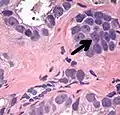

Intraductal carcinoma of the prostate with an infiltrative growth pattern may be morphologically difficult to distinguish from invasive cancer. One focus shows comedonecrosis (arrow), morphologically suggesting Gleason pattern 5 invasive carcinoma (a haematoxylin and eosin, b CK5/6)[19]